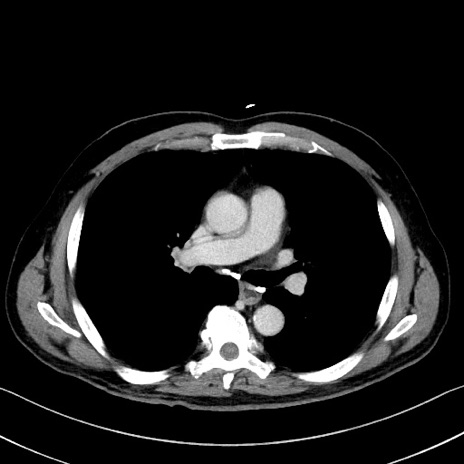

症例35(横断像)

【症例】70歳代 男性

【主訴】腹部膨満、嘔吐

【現病歴】昨日より腹部膨満感出現。本日増悪し、仙痛出現。嘔吐あり、受診。

【既往歴】糖尿病、胆摘後

【身体所見】BP 149/80mmHg、HR 74/min、BT 35.9℃、腹部:膨満、軟、圧痛なし。腸雑音減弱あり。上腹部正中切開瘢痕あり。

【データ】WBC 13500、CRP 1.72